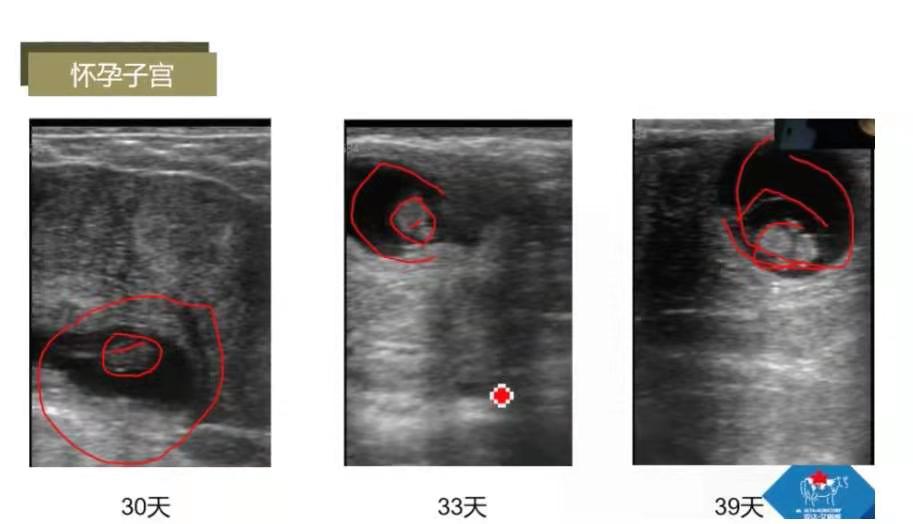

怀孕子宫:正常子宫呈灰色;怀孕子宫一侧角呈黑色,预示可能怀孕;2个角呈灰色,下面呈黑色。

怀孕子宫:怀孕30天子宫空腔内黑色为胚胎,直径1cm左右;33天胚胎直径为1.3cm左右,可检测到胎心;39天胚胎直径2cm左右。